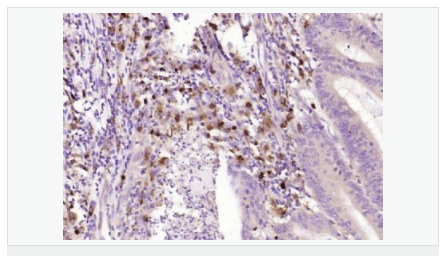

| 產品應用 | WB=1:500-2000 ELISA=1:5000-10000 IHC-P=1:100-500 IHC-F=1:100-500 ICC=1:100-500 IF=1:100-500 (石蠟切片需做抗原修復) not yet tested in other applications. optimal dilutions/concentrations should be determined by the end user. |

| 產品介紹 | This gene encodes an aldo-keto reductase that catalyzes the NADPH-dependent reduction of pteridine derivatives and is important in the biosynthesis of tetrahydrobiopterin (BH4). Mutations in this gene result in DOPA-responsive dystonia due to sepiaterin reductase deficiency. A pseudogene has been identified on chromosome 1. [provided by RefSeq, Jul 2008] Function: Catalyzes the final one or two reductions in tetra-hydrobiopterin biosynthesis to form 5,6,7,8-tetrahydrobiopterin. Subunit: Homodimer. Subcellular Location: Cytoplasm. Post-translational modifications: In vitro phosphorylation of Ser-213 by CaMK2 does not change kinetic parameters. DISEASE: Defects in SPR are the cause of dystonia DOPA-responsive due to sepiapterin reductase deficiency (DRDSPRD) [MIM:612716]. In the majority of cases, patients manifest progressive psychomotor retardation, dystonia and spasticity. Cognitive anomalies are also often present. The disease is due to severe dopamine and serotonin deficiencies in the central nervous system caused by a defect in BH4 synthesis. Dystonia is defined by the presence of sustained involuntary muscle contractions, often leading to abnormal postures. Similarity: Belongs to the sepiapterin reductase family. SWISS: P35270 Gene ID: 6697 Database links: Entrez Gene: 6697 Human Omim: 182125 Human SwissProt: P35270 Human Unigene: 301540 Human Important Note: This product as supplied is intended for research use only, not for use in human, therapeutic or diagnostic applications. |